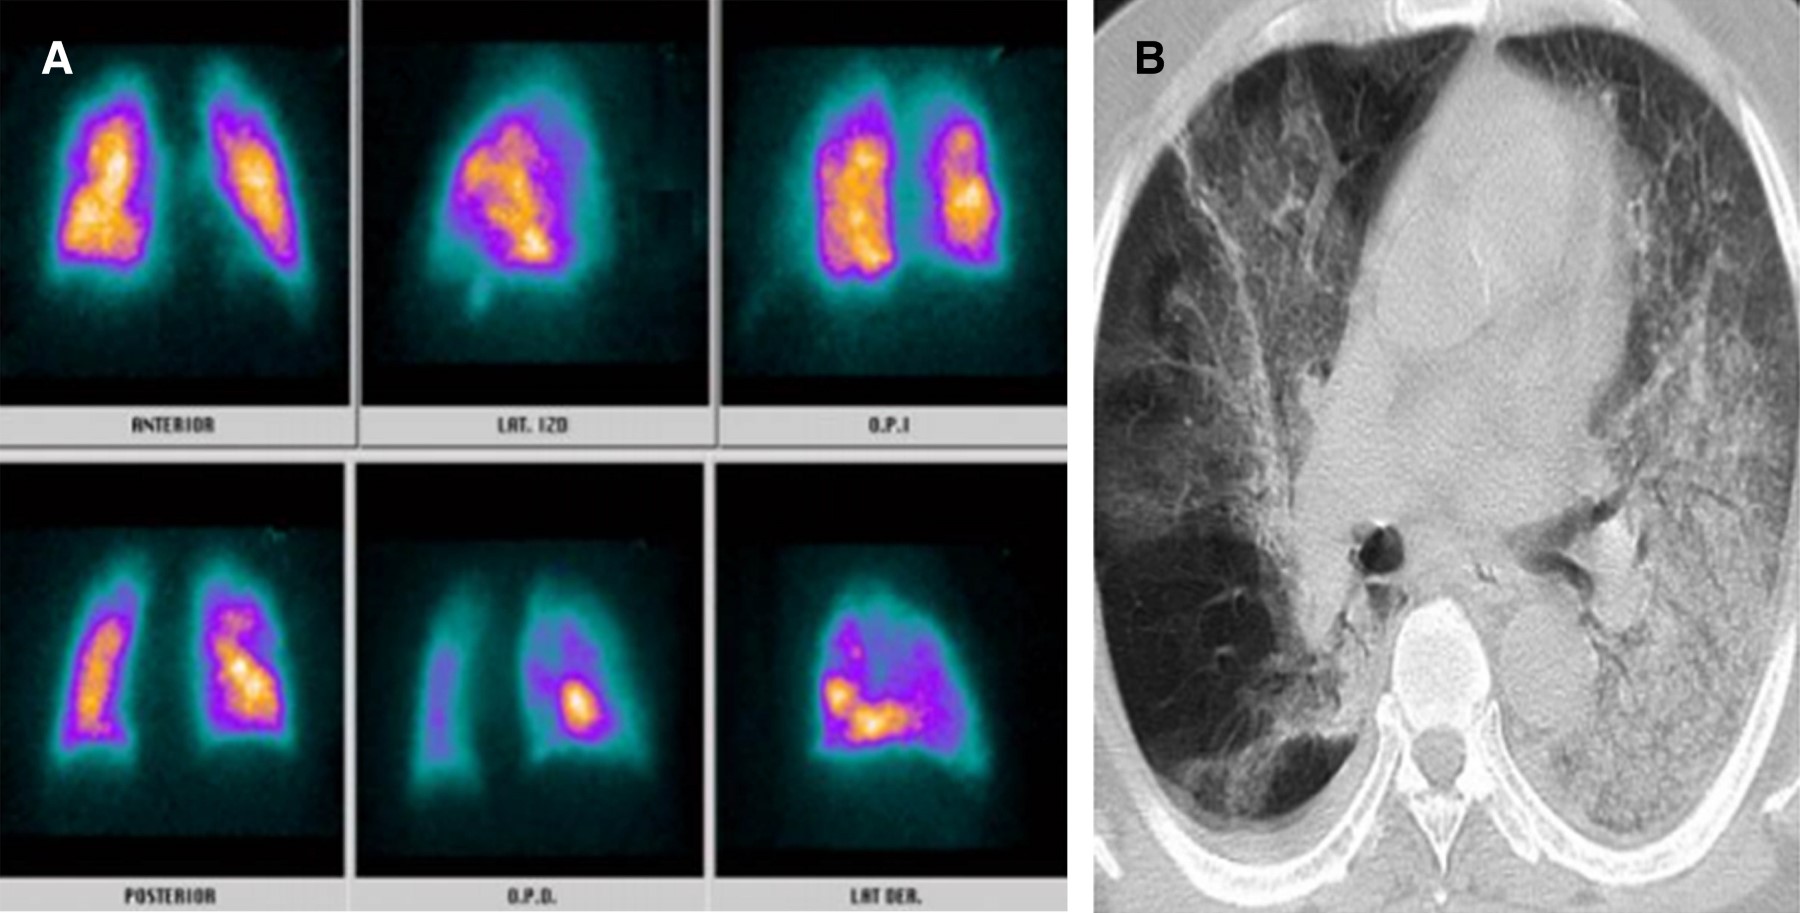

La infección por nuevo coronavirus es una entidad clínica altamente letal que trae consigo serias disfunciones celulares en primera línea de defensa, lo cual genera potentes mecanismos de hipercoagulabilidad mediados por reclutamiento de células inflamatorias.1 Uno de ellos direccionado por la disfunción del polimorfonuclear a partir del receptor 2 de enzima convertidora de angiotensina generado por la interacción de la fenilalanina ubicada en la porción 486 de la proteína de espiga del coronavirus, constituyéndose como el efecto más quimiotáctico existente, incluso superior al de la interleucina 8 (IL-8).2 A partir de esta situación, el reclutamiento del neutrófilo trae consigo la formación de una fina red inflamatoria inductora de integrinas denominadas NET (Neutrophil Extracellular Traps), produciendo activación de la vía intrínseca de la coagulación a partir del factor XII de Hageman. Adicionalmente, la muerte programada de dichas células, mediante la inducción de apoptosis, ocasiona liberación de histonas y restos de ADN, lo que precipita la formación de trombina.3,4 Por otro lado, la infección por nuevo coronavirus altera la respuesta del huésped al inóculo mediante modificación de los micro-ARN linfocitarios, lo que ocasiona disfunción del fagosoma natural en estadios de inmunocompetencia exacerbada o inmunosupresión manifiesta que a la postre desencadena estrés oxidativo, liberando grupos de proteínas de elevada movilidad (High Mobility Protein Box 1 [HMGB1]) y generando inflamación, coagulación y apoptosis.5 Pero, sin duda alguna, la linfopenia inducida por el coronavirus tipo 2 se constituye como el determinante más letal de trombosis mediante activación de la vía extrínseca e intrínseca de la coagulación, de la mano de un influjo descomunal de trombina. Se han identificado tres mecanismos de muerte celular programada en el linfocito de pacientes con la enfermedad por coronavirus del 2019 (COVID-19); uno de ellos es por activación del factor de transcripción nuclear y factor nuclear kappa beta, otra es por la activación del mitógeno p37 de la proteincinasa y la más deletérea mediante autofagocitosis determinante de un potente estado protrombótico.6 Con base en el conocimiento de los escenarios disfuncionales hematológicos durante la infección por nuevo coronavirus, se hace perentoria la predicción de enfermedad pulmonar tromboembólica, existiendo la duda razonable entre la prevención y la terapia antitrombótica, motivo por el cual la presencia de marcadores de actividad de fibrinolítica debe ser validada en tiempo presente y real. Teniendo en cuenta la mejor sensibilidad y especificidad disponible, las diferentes técnicas de enzimas líticas de inmunoensayo, hemaglutinación y látex deben someterse a consideración durante la estratificación diagnóstica.7,8 Una vez discriminados los pacientes con SARS-CoV-2 con pretest clínico medio para enfermedad pulmonar tromboembólica con reporte de dímero D por técnica de látex positivo y cuyos resultados de angio-TAC descartaron tromboembolia pulmonar (TEP); se les documentó, desde el punto de vista imagenológico, los defectos segmentarios de distribución vascular con morfología triangular de base externa y vértice interno por medicina nuclear, los cuales se correlacionaron muy de cerca con hallazgos en escanografías simples de tórax con atelectasias, efusión pleural y condensaciones, así mismo la presencia de alta probabilidad para TEP se validó por criterios de PISAPED (Figura 1, 2, 3, 4, 5, 6 y 7).9

Figura 1

Figura 2

Figura 3

Figura 4

Figura 5

Figura 6

Figura 7